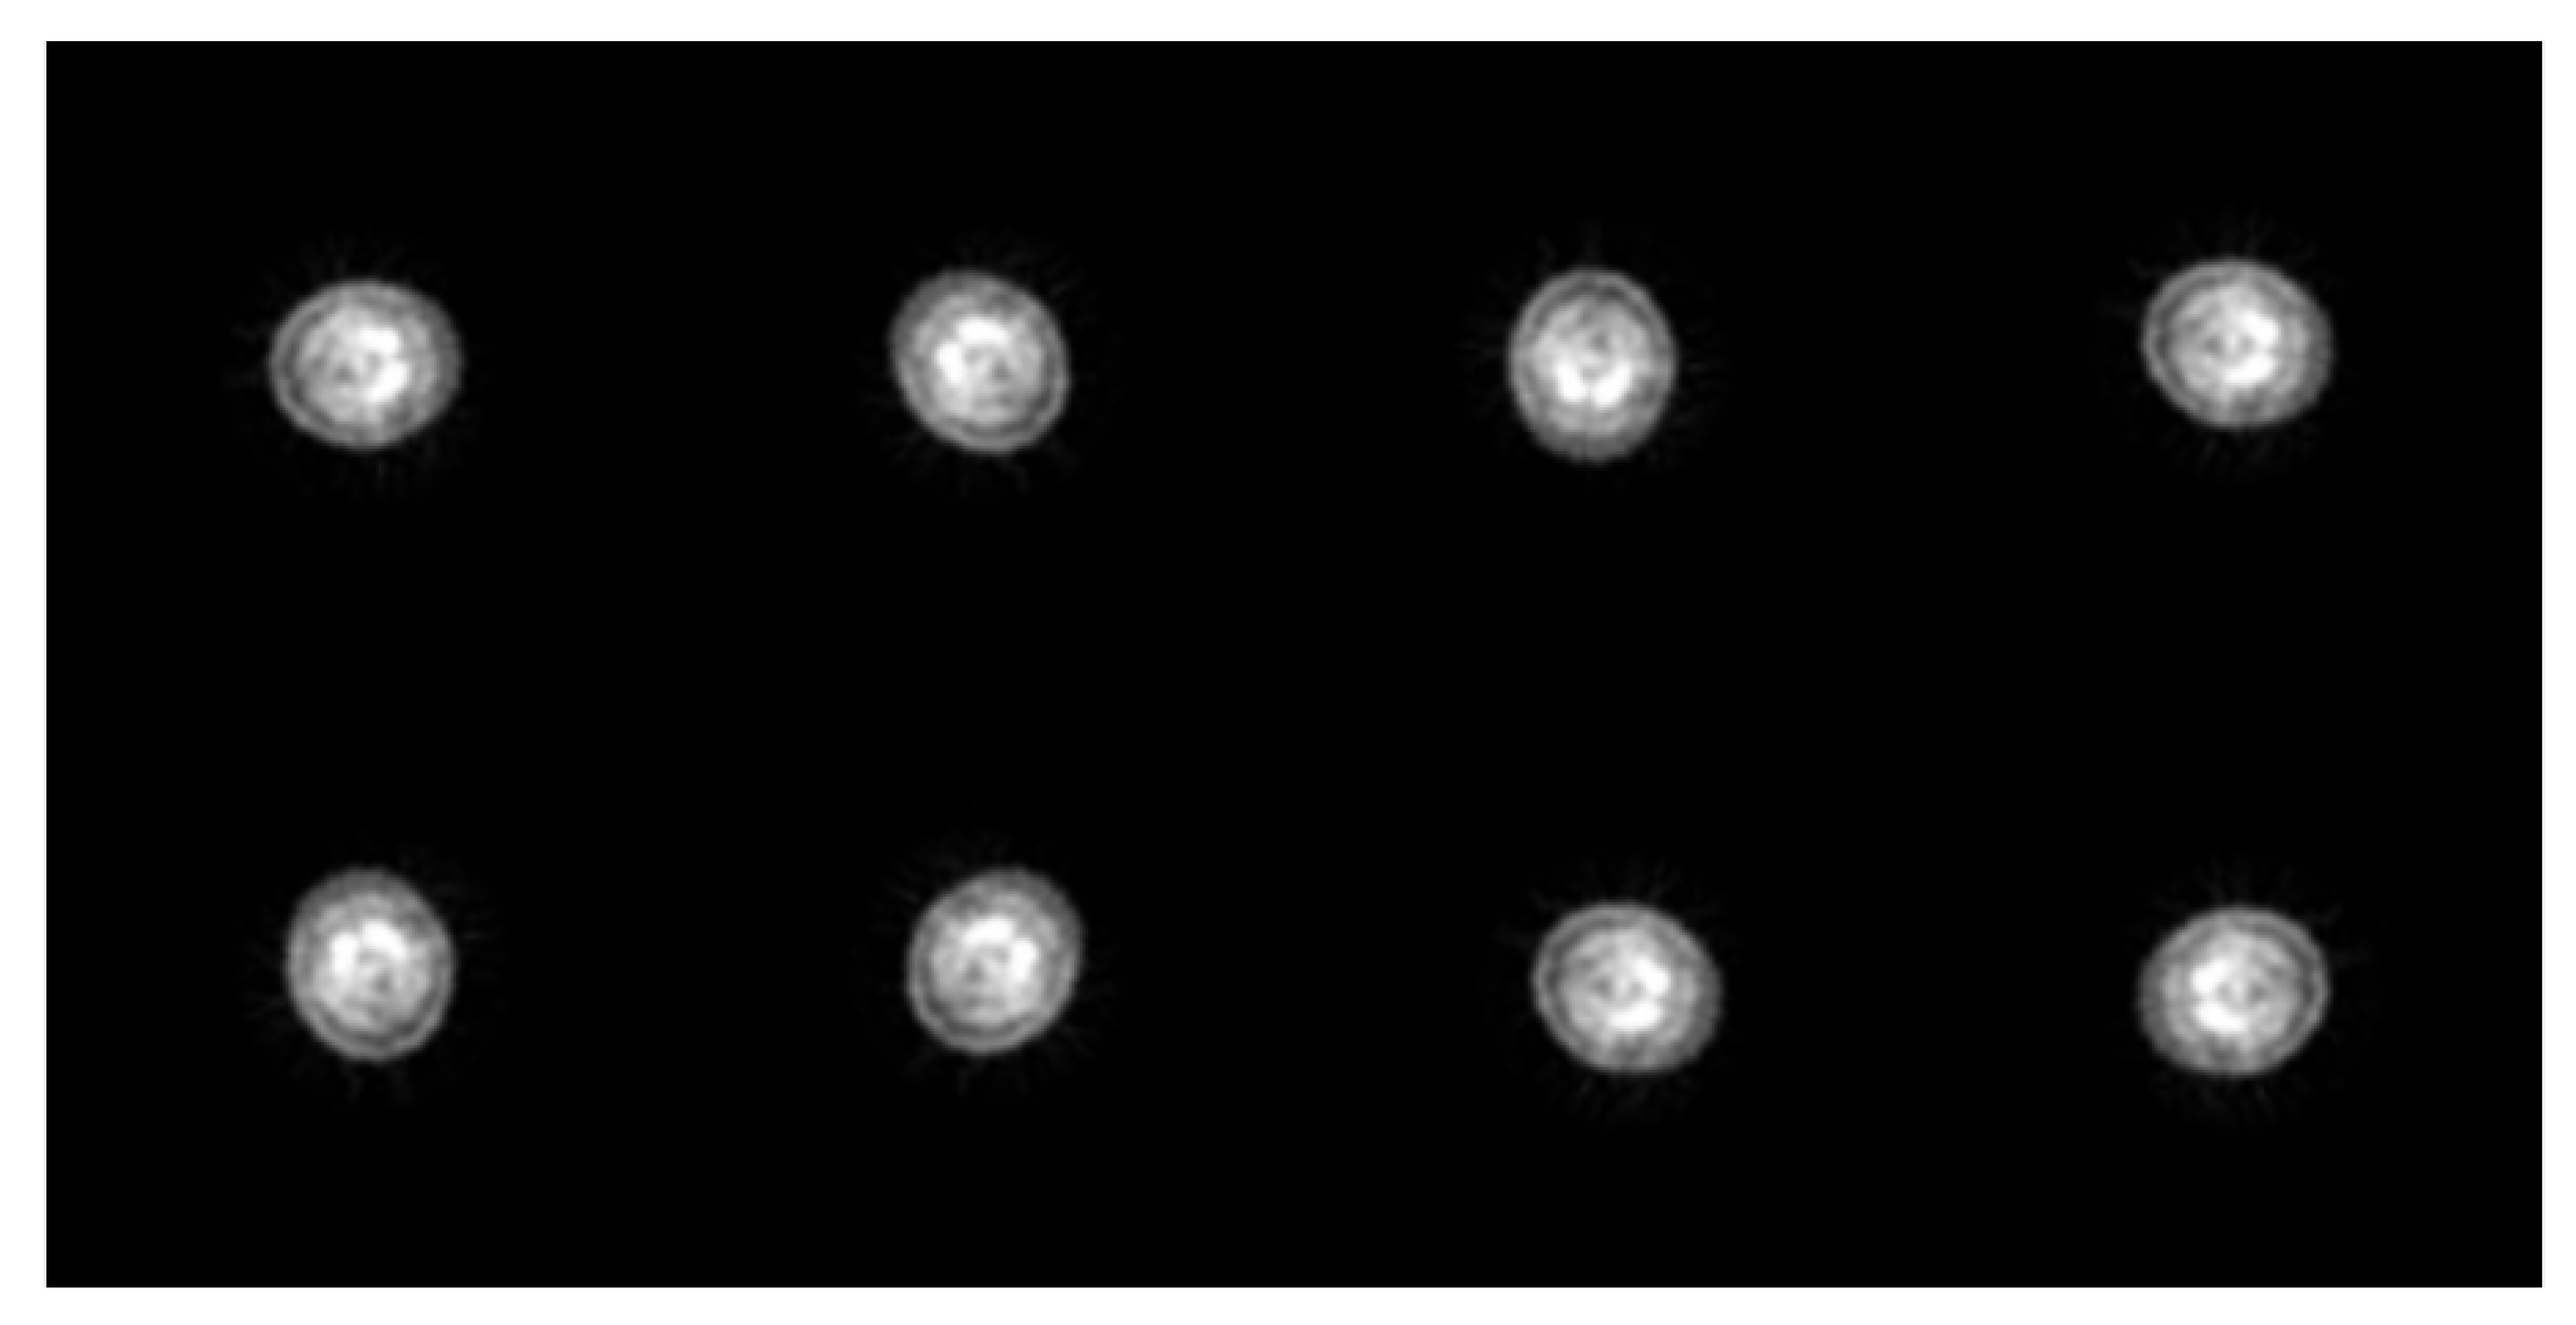

2.4. Popular Pre-trained Models in CNN

2.4.1. AlexNet